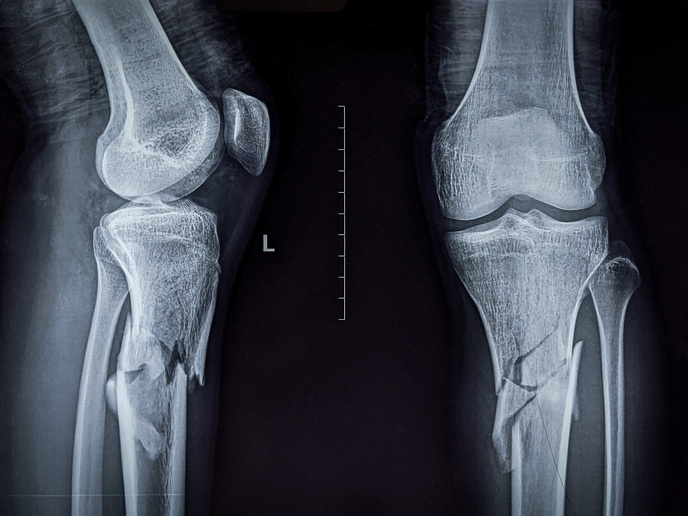

But MULT2D did more than deliver new insights, it also developed predictive tools to accurately assess one’s risk of bone fracture. For example, an innovative coarse-grained molecular dynamics model can be used to examine such important indicators as extra- and intra-fibrillar mineralisation. Another tool uses advanced finite element models and new algorithms to analyse trabecular bone architectures – also a key indicator for predicting the probability of fracture. “These tools are especially relevant for diabetic and ageing populations and have opened new paths for research, diagnosis and treatment,” notes Vaughan. The project’s work has been recognised by national and international bodies and received several awards, including the Engineers Ireland Medal and Best Presentation in Biomechanics at the European Orthopaedic Research Society(opens in new window) Conference. They have also been featured in publications, such as ‘Nanoscale’(opens in new window), ‘Scientific Reports’(opens in new window), and ‘Bone’(opens in new window).